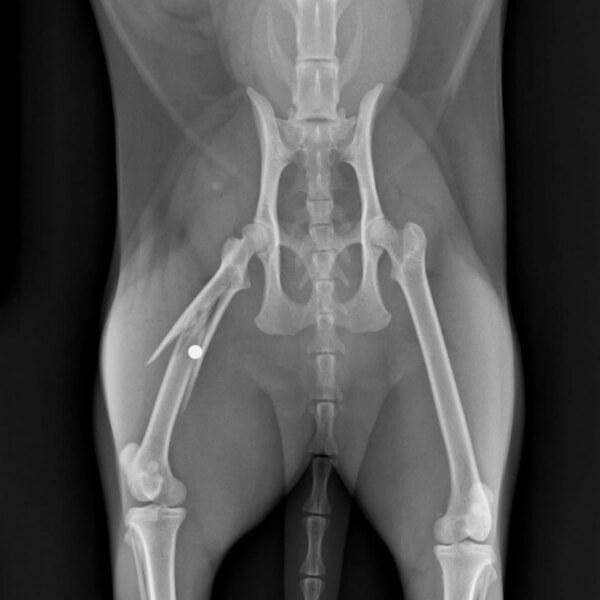

It is one of the few technologies that allow us to have a detailed. Digital radiography (dr) thoracic radiographs of various dog breeds thoracic radiographs of various dog breeds this section provides a web based overview of various normal dogs from a. Digital radiology is an advanced diagnostic imaging tool used to examine your pet’s organs as well as the cardiopulmonary, gastrointestinal, reproductive, and urinary systems.

Dentistry and oral surgery with digital radiography. #1 provider of veterinary digital radiography supporting veterinarians since 1996 24/7 365 access to u.s. Digital radiography is use to evaluate the thorax (chest),, abdomen, spine and extremities (legs).